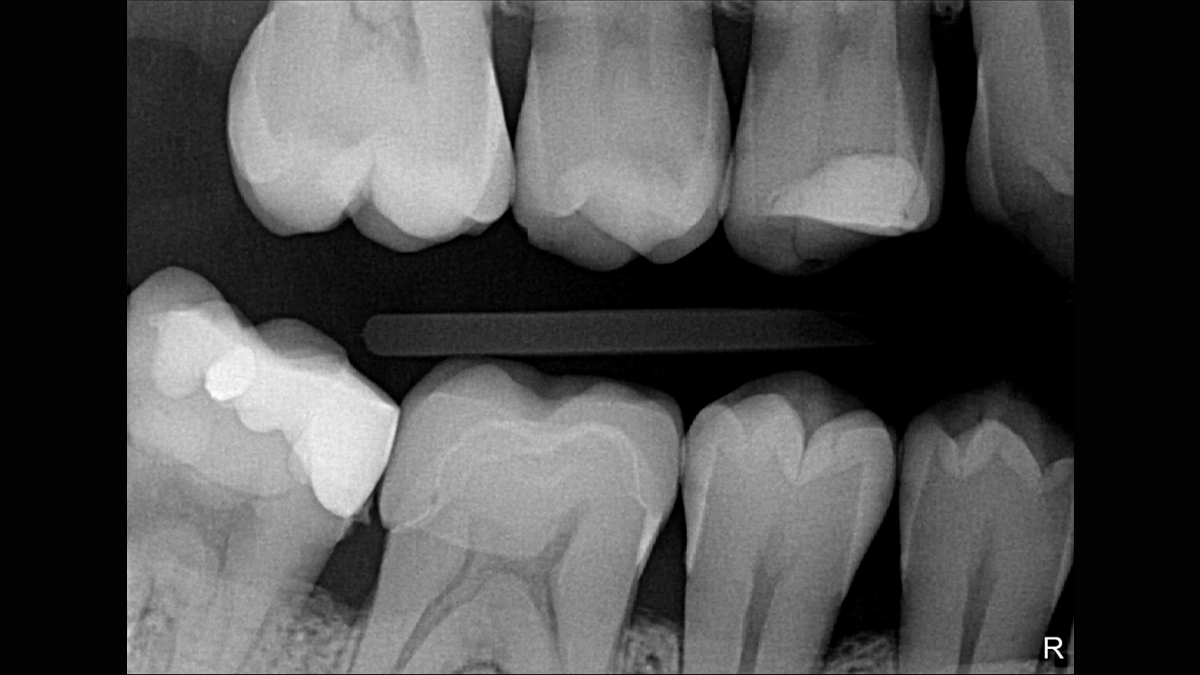

Xios XG Supreme proporciona una resolución teórica de 33 pl/mm y un tamaño de píxel de 15 μm que ofrece una excelente calidad de imagen sin el tiempo de espera adicional causado por un proceso de revelado o escaneo.

La excepcional calidad de las imágenes es solo el comienzo con los sensores intraorales Xios XG Supreme. El deslizador de nitidez dinámica le permite ajustar las configuraciones de su diagnóstico en términos de nitidez. Hay disponibles opciones adicionales del deslizador para modificaciones de brillo y contraste. Después de la configuración, las imágenes se muestran de manera eficiente para mejorar sus capacidades de diagnóstico, lo que le ahorra tiempo valioso. Un solo clic del mouse le permite obtener la imagen correcta para cada situación de tratamiento y mejor soporte clínico.

Los sensores Xios XG Supreme tienen cinco opciones diferentes de filtro: odontología general, endodoncia, periodoncia, restauración y caries. Estas vistas clínicamente específicas están diseñadas para optimizar su diagnóstico, mejorando la imagen para satisfacer sus necesidades.